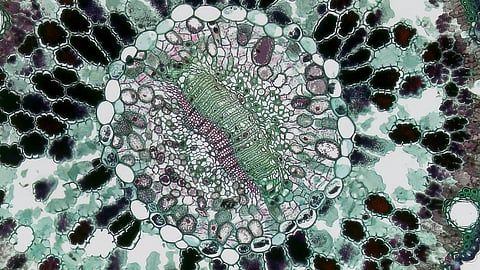

Investigators tracked protein changes in individual cells as they developed from stem cells into heart cells, and revealed important differences in the structure and metabolism of these cells as compared with naturally occurring heart cells. While single-cell RNA methods are widely available now and allow thousands of genes to be assessed simultaneously, there is very little data looking at the inventory of proteins within single cells simultaneously. Cedars-Sinai is pioneering new single-cell technologies at its Innovation Center and using the most advanced protein analysis equipment to get more resolution of proteins within single cells for the first time.

We looked at cardiomyocytes, which are heart muscle cells. We discovered two distinct types of cardiomyocytes and found rare hybrid cells expressing both heart- and neuron-related proteins, suggesting that heart cells may have more protein flexibility than previously thought. These discoveries will help us create more detailed, realistic models of human heart cells.